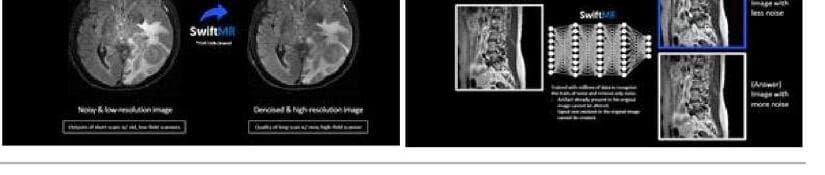

제품 썸네일

핵심 화면/제품 이미지를 간단히 확인할 수 있습니다.